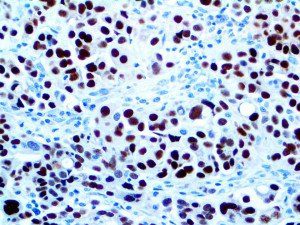

It is the ICU physician who is most likely to witness one of the deadliest manifestations of the abnormal immunological response, the cytokine storm syndrome (CSS). This response is also referred to by some as the cytokine release syndrome (CRS). CSS is characterized by continuous activation and expansion of macrophage and lymphocyte populations, which secrete large amounts of cytokines, causing the cytokine storm. This massive cytokine release is akin to hemophagocytic lymphohistiocytosis (HLH) disease, a syndrome characterized by initial unchecked and persistent activation of cytotoxic T lymphocytes and NK cells.

Clinical and laboratory manifestations of HLH include fever, enlarged liver and/or spleen, neurologic dysfunction, coagulopathy, liver dysfunction, cytopenias (i.e., low levels of erythrocytes, leukocytes, and/or platelets), hypertriglyceridemia, hyperferritinemia, hemophagocytosis, and eventually diminished NK cell activity as the immune system becomes progressively paralyzed. HLH can be familial (primary HLH) or secondary to another disease process (sHLH), such as rheumatic disease, in which it is referred to as macrophage activation syndrome (MAS, characterized by elevated ferritin).